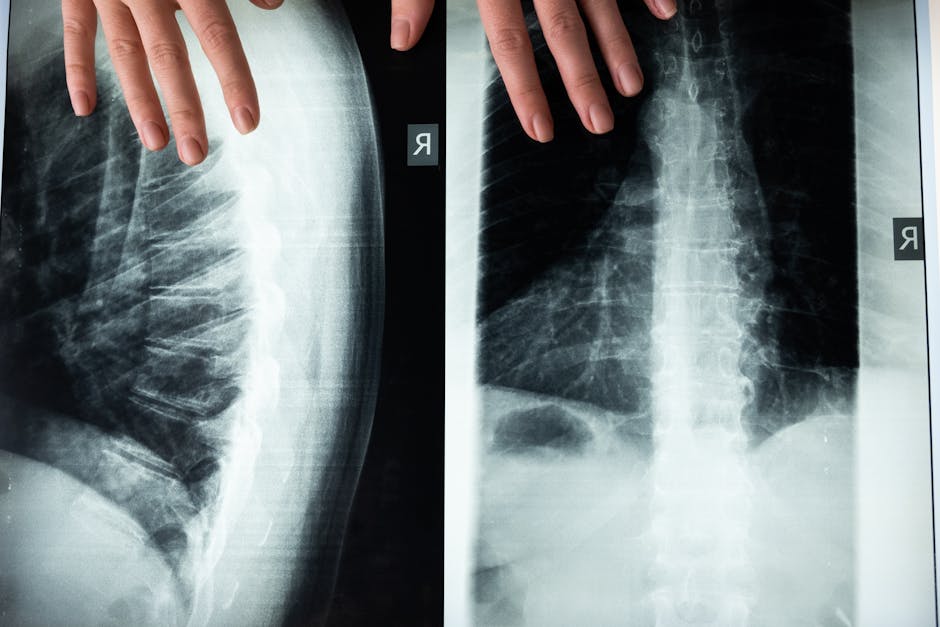

Hypophosphatemic osteomalacia is a rare metabolic bone disorder characterized by softening of the bones due to defective mineralization. The condition is often caused by genetic mutations or acquired through certain medical conditions, such as vitamin D deficiency or kidney disease. Despite its rarity, HO has a significant impact on the lives of those affected, causing chronic pain, muscle weakness, and increased risk of fractures. The condition is frequently misdiagnosed or underdiagnosed, leading to delayed treatment and exacerbated symptoms. As the global survey highlights, the inconsistent management of HO is a pressing concern that requires immediate attention from healthcare professionals, policymakers, and patient advocacy groups.